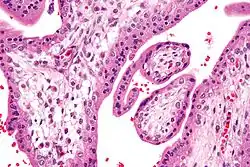

Hofbauer cells are oval eosinophilic histiocytes[1] with granules and vacuoles found in the placenta, which are of mesenchymal origin, in mesoderm of the chorionic villi, particularly numerous in early pregnancy.

Under histology sections, Hofbauer cells have appeared with discernible amount of cytoplasm.